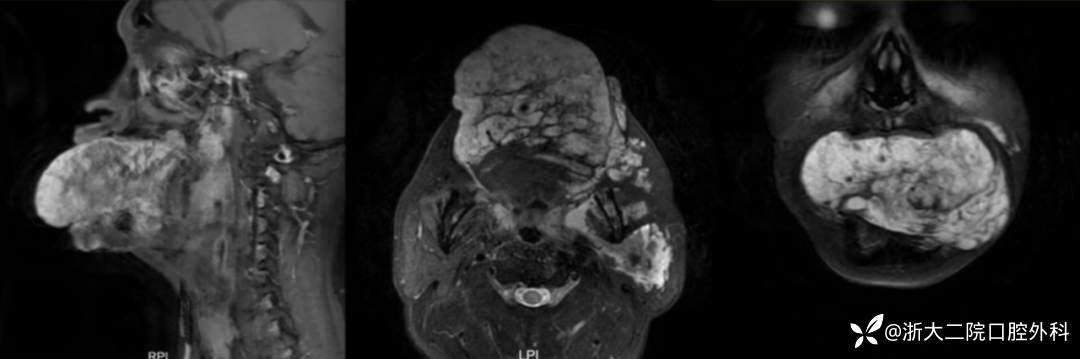

那么是否会是囊肿或其他血管畸形?治疗团队随即安排患者进行了舌部的增强磁共振检查,结果提示病灶为静脉畸形,且遍布患者左侧的舌-咽旁、颌面间隙、颌面部软组织及左侧腮腺。

患者 MRI 结果